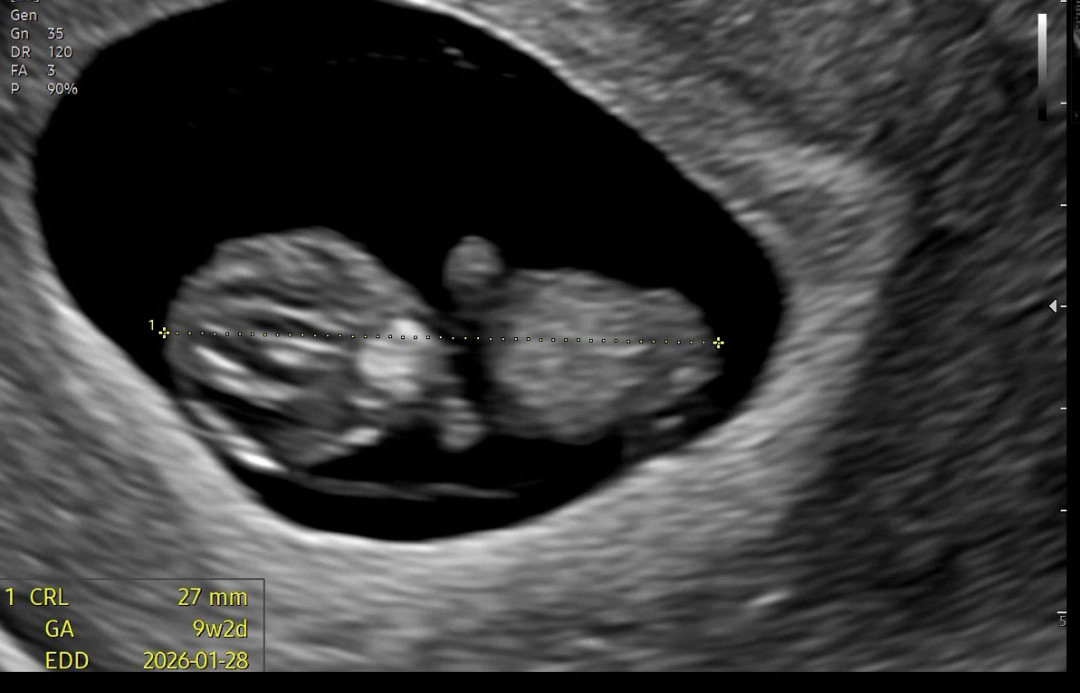

9주 2일차 젤리곰 너무 귀여워요

9주 2일차 꼬물꼬물 젤리곰 보고왔어요 너무 귀엽지않나요 !!!!

배초음파 잘 안보일것같다고 하셔서 질초음파로 봤어요 ^^